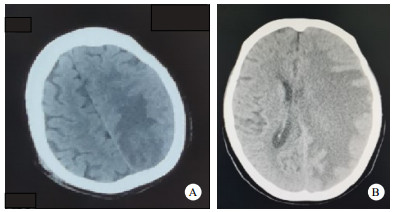

A:3月29日头CT示左侧额、顶、枕叶片状水肿;B:4月16日头CT示大脑左半球大片不规则低密度灶,其内团块样混杂密度;大脑镰下疝 图 1 患者头部CT检查结果

患者女性,71岁,因“右侧肢体乏力伴言语不利4 d,咳嗽伴发热3 d”于2021年3月29日第一次入院。既往高血压,尿毒症透析2年。查体:神清,言语不利,双肺底湿啰音,右侧肢体肌力Ⅰ级且巴氏征阳性。白细胞10.72×109/L,C反应蛋白44.26 mg/L,降钙素原1.10 ng/mL,肌酐948.3 μmol/L,尿素28.22 mmol/L,癌胚抗原5.01 ng/mL。G、GM试验阴性,PPD阴性,结核杆菌特异性细胞免疫反应检测(TB-IGRA)阳性。外院CT见左侧额、顶、枕叶片状水肿(图 1A),左肺空洞。入院连续3 d痰培养未见异常。支气管镜见左肺下叶开口黏膜充血。肺泡灌洗液培养出肺炎克雷伯菌,高通量测序示肺炎克雷伯菌(序列数9844)。经皮肺穿病理示纤维组织伴淋巴细胞浸润。头核磁示左枕叶及额颞叶异常信号。脑脊液培养5 d无细菌,高通量测序示肺炎克雷伯菌(序列数31)。诊断为肺脓肿、脑脓肿(肺炎克雷伯菌)。患者先后经头孢曲松钠美罗培南抗感染以及床旁血滤2周后未再发热自动离院。4月16日患者因“嗜睡伴发热1 d”返诊,体温峰值为38.5℃,查体躁动,失语,右侧肢体肌力0级。CT见大脑左半球大片低密度灶,其内团块样混杂密度,大脑镰下疝(图 1B);左肺空洞消失。继续给美罗培南抗感染及床旁血滤治疗。4月19日患者神志转清,无发热,可简单应答,增强核磁见左侧额顶叶多发脓肿,有窦道连通(图 2A),家属拒绝进一步手术干预。保守治疗1个月余后言语基本流利,右侧肢力Ⅱ-Ⅲ级,复查头核磁脓肿减小,脑疝消失(图 2B)。6月30日右侧肢体Ⅴ级转入下级医院。2个月后随访,患者症状未再反复。